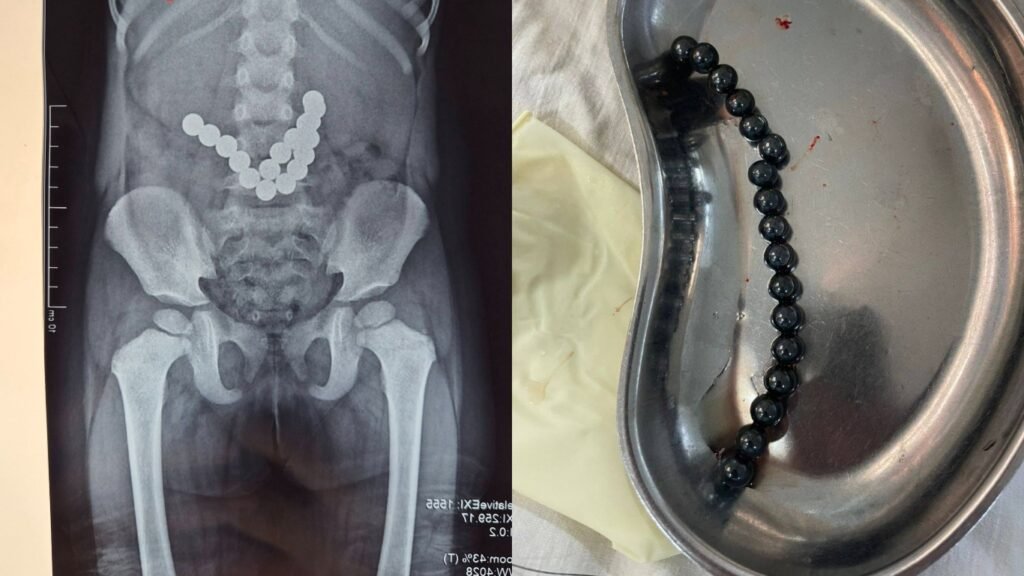

Проглотил 17 магнитов. В Оше прооперировали 2-летнего ребенка

В Оше прооперировали 2-летнего ребенка, проглотившего магнит от игрушки. Об этом сообщила Ошская межобластная детская клиническая больница.

По данным медучреждения, ребенок в течение трех дней периодически рвал, после чего родители обратились в больницу. По результатам рентген-обследования было установлено, что в кишечнике находятся несколько инородных предметов. Врачи срочно провели операцию и извлекли 17 игрушечных магнитов.